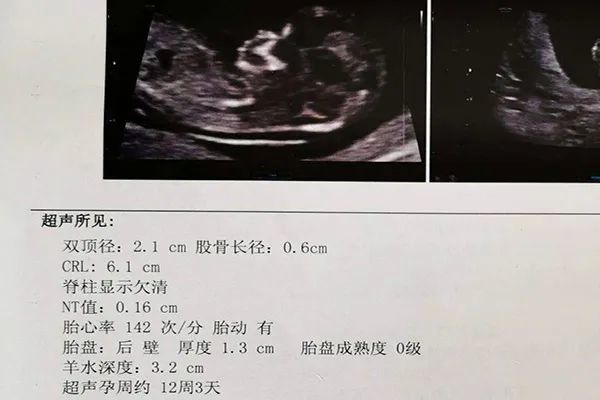

怀男孩nt图片 胎儿,怀男孩nt图片男宝

今天去医院检查了nt医生说胎儿状况很好

nt可以看男女吗娱乐一下

nt顺利通过,有帮忙会看男宝女宝的吗?

3个月nt数据暗示胎儿性别,12周nt如何看出男孩女孩?